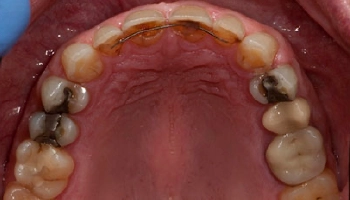

4 Implant Retained Maxillary Denture

Before image of a maxillary denture, showing missing teeth. After image of a maxillary denture supported by four implants. Before and after images of a maxillary denture with implants.